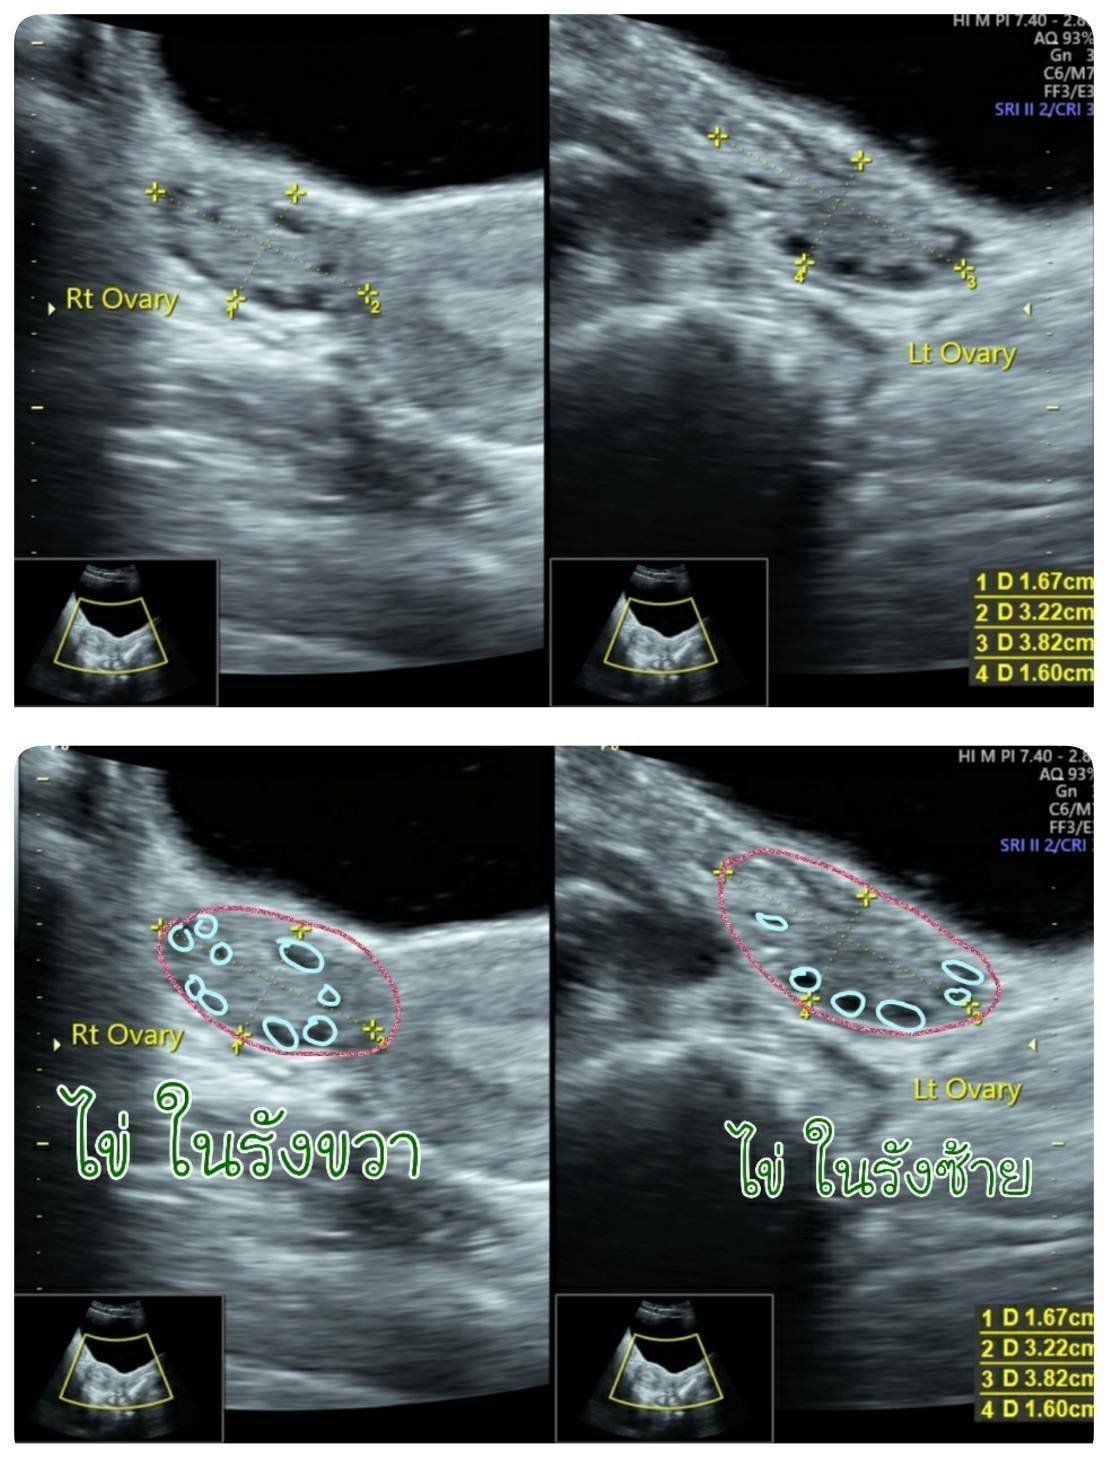

ภาพตรวจอัลตร้าซาวด์รังไข่ผ่านทางหน้าท้อง

ตรวจหาเนื้องอก ถุงซีสต์ วัดขนาดรังไข่ ประเมินไข่ในรังไข่